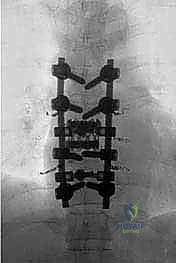

المرحلة الثانية: تثبيت المسامير وبناء الدعامة المؤقتة

قبل البدء في إزالة الفقرة المصابة، يجب تأمين استقرار العمود الفقري. يتم إدخال مسامير التيتانيوم (Pedicle Screws) في الفقرات السليمة فوق وتحت الورم، وتوصيلها بقضبان معدنية مؤقتة لضمان عدم انهيار العمود الفقري أثناء الاستئصال.